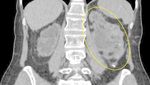

Setelah dilakukan pemeriksaan, dokter menemukan batu ginjal kiri besar berukuran 13,6 cm x 8 cm x 6,8 cm. Dokter juga menemukan adanya beberapa batu kecil di ginjal kanan. (Foto: BMC Urology)

Dengan mempertimbangkan fungsi ginjal yang masih ada serta risiko gangguan aliran urin akibat ukuran batu yang besar, tindakan operasi dinilai rasional. Karena fungsi ginjal masih dapat diselamatkan, nefrektomi (pengangkatan ginjal) tidak dipertimbangkan. (Foto: BMC Urology)

Pemulihan pasca operasi berlangsung tanpa komplikasi. CT scan tindak lanjut yang dilakukan setelah 9 bulan menunjukkan keberhasilan tindakan. (Foto: BMC Urology)